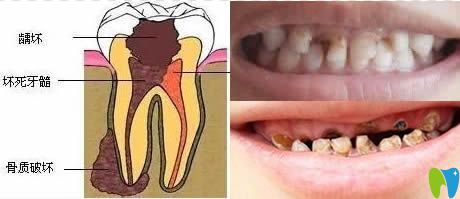

我們通過(guò)下圖來(lái)看看齲齒發(fā)展速度有多快?

齲齒發(fā)展過(guò)程圖解

1、先是齲壞于牙釉質(zhì)層;2、發(fā)展到牙本質(zhì),這時(shí)已對(duì)冷熱刺激感到敏感;3、牙髓炎階段,開(kāi)始自發(fā)陣痛;4、由牙髓感染導(dǎo)致根尖發(fā)炎疼痛,面部腫脹;5、牙冠破壞,根尖病變,牙頜骨質(zhì)開(kāi)始遭到破壞。

兒童乳牙齲壞真實(shí)寫(xiě)照